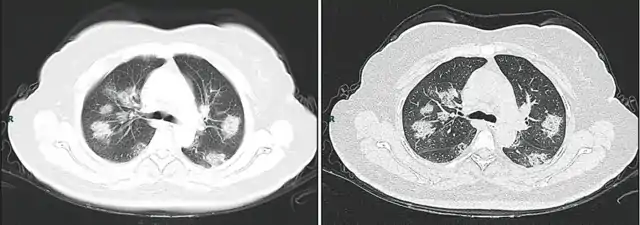

- Billedbeskrivelse på Commons : "CT imaging of rapid progression stage. A 50 years old female with anorexia, fatigue, muscle soreness, nasal congestion and runny nose for 1 week, sore and itching throat for 2 days. Laboratory test: increased erythrocyte sedimentation rate (25 mm/h), normal white blood cells (4.08 × 109/L), decreased lymphocytes (0.96 × 109/ L), increased C-reaction protein (60.8 mg/L). Imaging examination: a (thin layer CT) and b (high-resolution CT) showed multiple patchy and light consolidation in both lungs and grid-like thickness of interlobular septa"